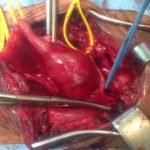

Une fois la thrombose aortique diagnostiquée, une prise en charge adéquate est cruciale pour prévenir les complications graves. Les options de traitement varient en fonction de la gravité de la condition et peuvent inclure des interventions médicales et chirurgicales. Le traitement médical repose principalement sur la gestion des facteurs de risque athéromateux, tels que l’hypertension, le diabète, l’hypercholestérolémie et le tabagisme.

Dans les cas plus sévères, où l’obstruction de l’aorte est significative ou lorsque des complications telles qu’un anévrisme sont présentes, une intervention chirurgicale peut être nécessaire. Les options chirurgicales comprennent la thrombectomie, qui consiste à retirer le caillot sanguin, et la mise en place de stents pour maintenir l’artère ouverte. Dans certains cas, une chirurgie de pontage aortique peut être réalisée pour contourner les sections obstruées de l’artère.